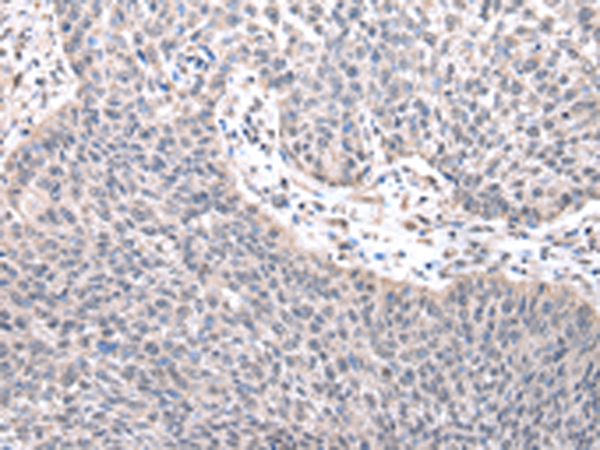

IHC positive control: |

Human lung cancer |

IHC Recommend dilution: |

25-100 |